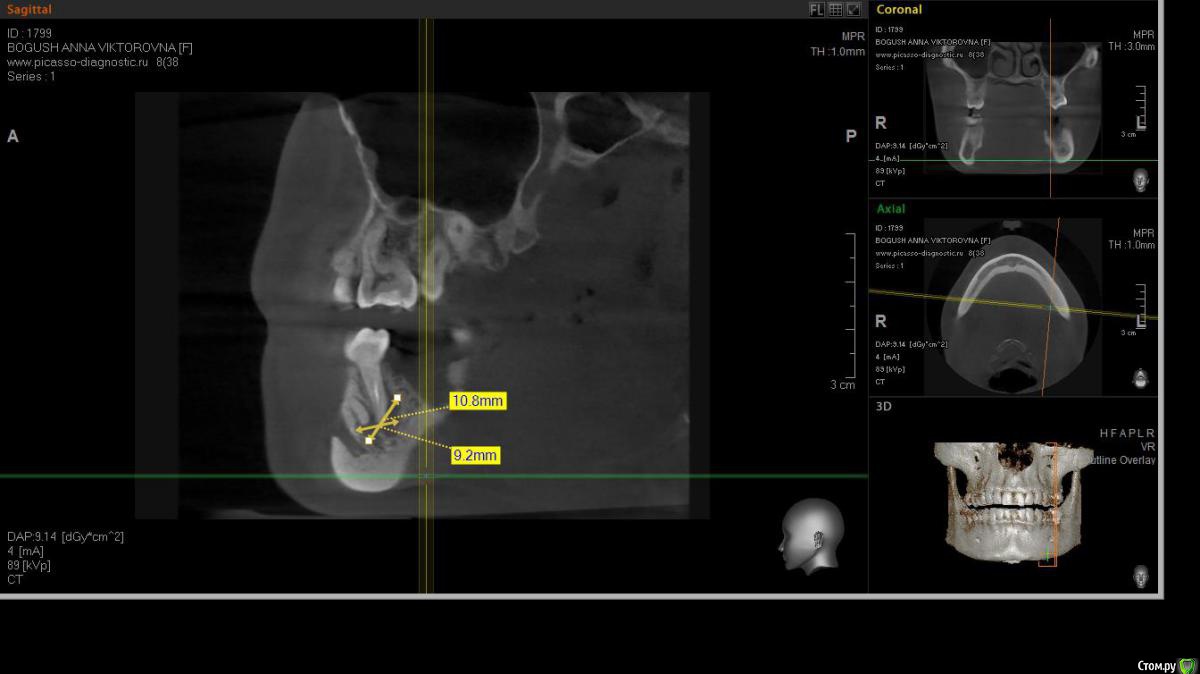

cor Опубликовано 2 апреля, 2016 Поделиться Опубликовано 2 апреля, 2016 Доброго времени суток, коллеги! Каков Ваш прогноз? Удалять пац. совсем не хочет(знакомая). Есть хоть какая то вероятность, что ретрит поможет? <script> </script> Ссылка на комментарий

cor Опубликовано 2 апреля, 2016 Поделиться Опубликовано 2 апреля, 2016 (изменено) гадская вирусятина на компе мешает. Нет конечно желающих. Но если ретрит будет, то делать его буду я. Но слабо верю в положительный исход(( Изменено 2 апреля, 2016 пользователем cor Ссылка на комментарий

Гарриевич Опубликовано 3 апреля, 2016 Поделиться Опубликовано 3 апреля, 2016 Доброго времени суток, коллеги! Каков Ваш прогноз? Удалять пац. совсем не хочет(знакомая). Есть хоть какая то вероятность, что ретрит поможет? шансов не меньше чем тут Ссылка на комментарий

St. Опубликовано 3 апреля, 2016 Поделиться Опубликовано 3 апреля, 2016 Доброго времени суток, коллеги! Каков Ваш прогноз? Удалять пац. совсем не хочет(знакомая). Есть хоть какая то вероятность, что ретрит поможет? Вполне есть смысл попробовать. Вероятность есть, только "заживать" будет долго. Ссылка на комментарий

cor Опубликовано 5 апреля, 2016 Поделиться Опубликовано 5 апреля, 2016 Почему?Наверное потому что такие объемные очаги ещё не перилечивал. Но деваться некуда, будем пробовать. Ссылка на комментарий

Л Ю С Я Опубликовано 5 апреля, 2016 Поделиться Опубликовано 5 апреля, 2016 Наверное потому что такие объемные очаги ещё не перилечивал. Но деваться некуда, будем пробовать.Уже не раз писали, что размер не имеет значения)))). Не надо перелечивать очаг. Ваша задача пройти, правильно сформировать, очистить и запаковать каналы, а также правильно восстановить коронковую часть. И будет вам хилинг))) 2 Ссылка на комментарий